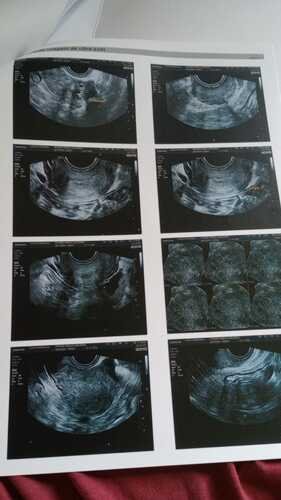

Foi aí que diagnosticaram que eu tenho endometriose profunda, faço uso de medicação contínua, o Allurene que é um medicamento que contém hormônio (dienogeste) para o tratamento dos sintomas dolorosos das lesões da endometriose (migração e crescimento do tecido da parede interna do útero fora da cavidade uterina), o qual não é fornecido pela farmácia do SUS por ser de alto custo e preciso comprar mensalmente. Sem essa medicação sofro de fortes hemorragias, barriga fica muito inchada, tenho fortes cólicas e muitas vezes preciso ser internada pra tomar medicação e suportar a dor.

Já tentei 03 vezes o pedido da realização da cirurgia, que foi negada pelo SUS. Então, juntei recursos e fui consultar com um especialista particular, Dr Igor Chiminácio, na cidade de Pato Branco-PR. Este médico afirmou ser possível a realização da cirurgia, será muito delicada, pois é preciso ser retirado o meu útero, os dois ovários, apêndice, parte do meu umbigo e descolar o mesmo do intestino, pois esta todo aderido, inclusive o meu nervo ciático esta prejudicado em decorrência dessas aderências. Estou aguardando a autorização de uma ressonância pra saber se será necessário a retirada de parte do intestino.